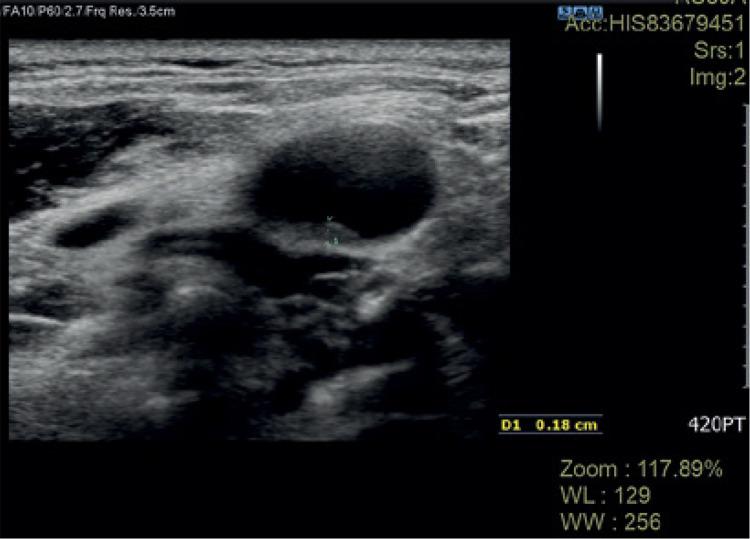

https://cdn.ncbi.nlm.nih.gov/pmc/blobs/1b43/9494789/1446f0eea8ee/RU-60-47707-g001.jpg